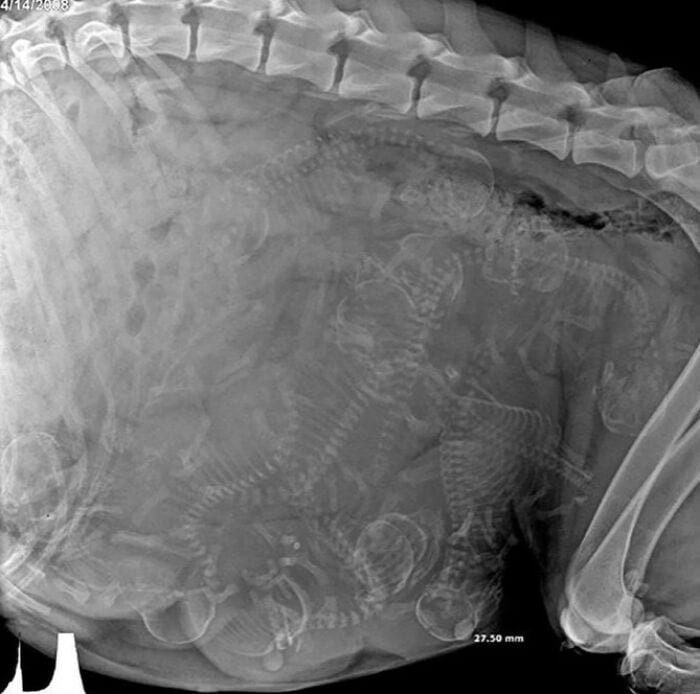

9. Рентгеновский снимок, показывающий беременность собаки

Нам удалось насчитать 9 щенков, хотя в комментариях были разные варианты.

А вам как кажется, сколькими щенками беременна эта собака? 🩻